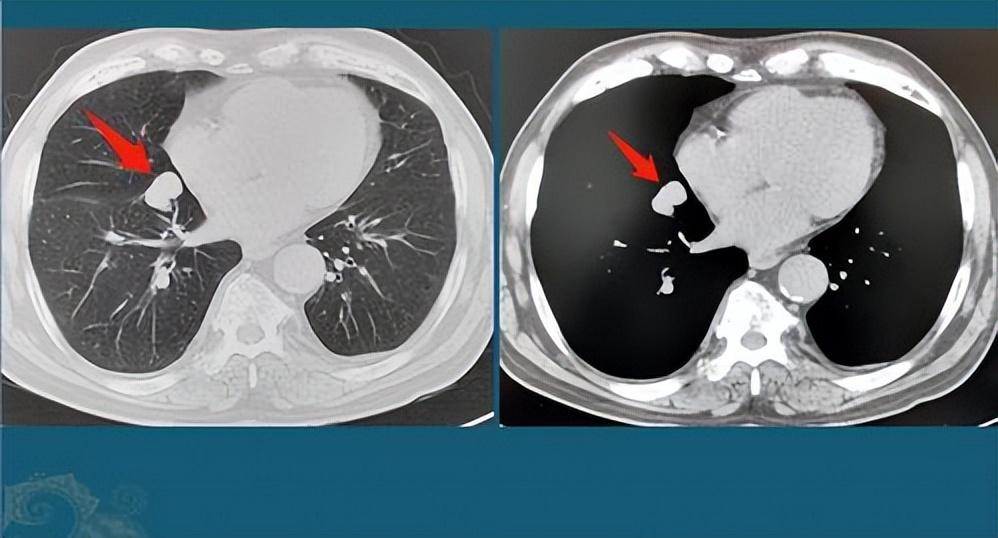

肺結(jié)節(jié)是指肺部出現(xiàn)的直徑小于3厘米的圓形或類圓形病灶,大多數(shù)肺結(jié)節(jié)是良性的,但部分可能需要治療,肺結(jié)節(jié)的癥狀因個體差異而異,部分患者在早期可能無任何癥狀,因此定期進行體檢至關(guān)重要。